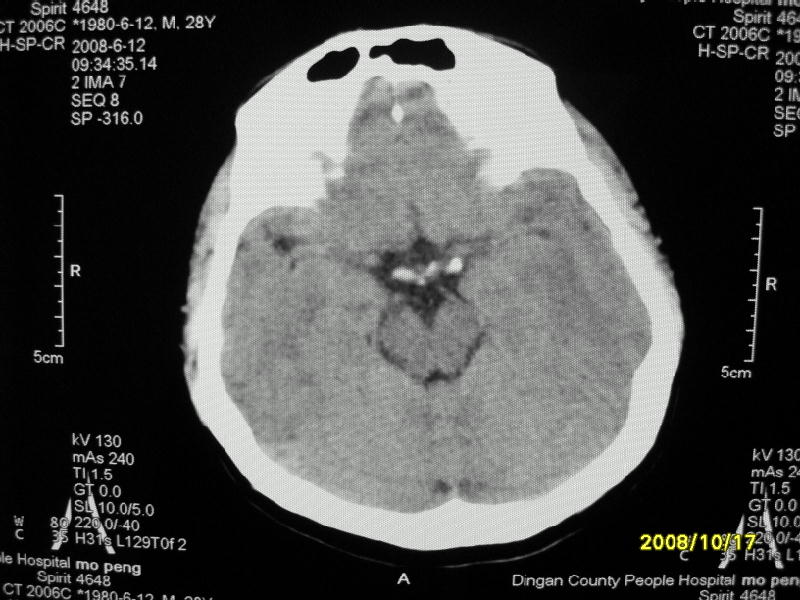

检查名称:     ct颅脑平扫           男     28岁

表现:左顶叶见斑点状致密影。边缘清,大小约0。3*1。0cm,余脑实质密度及灰白质结构示见异常。脑室系统大小,形态,密度未见异常。脑沟。脑裂。脑池未见异常密度影。中线结构无移位。

印象:左顶叶少许钙化灶

左顶叶见斑点状致密影。边缘清,大小约0。3*1。0cm,余脑实质密度及灰白质结构示见异常。脑室系统大小,形态,密度未见异常。脑沟。脑裂。脑池未见异常密度影。中线结构无移位。

印象:左顶叶少许钙化灶。